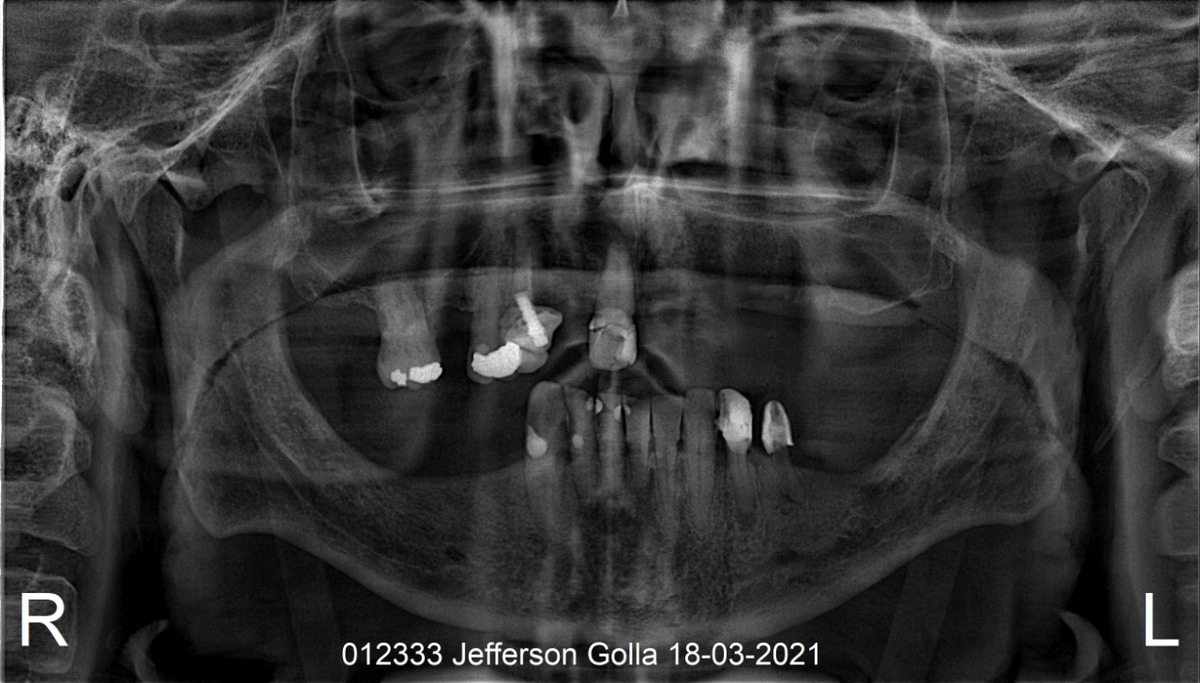

PRÓTESE TOTAL FIXA EM IMPLANTES

J.G.